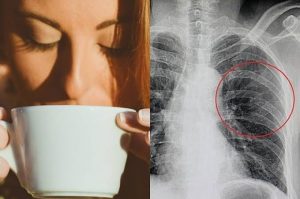

Terlalu Banyak Konsumsi Kopi Dinilai Buat Tulang Keropos

detektifswasta.xyz – Indonesia Berapa banyak Anda meminum kopi dalam sehari? Kopi memang punya manfaat sebagai pembangkit mood dan energi.